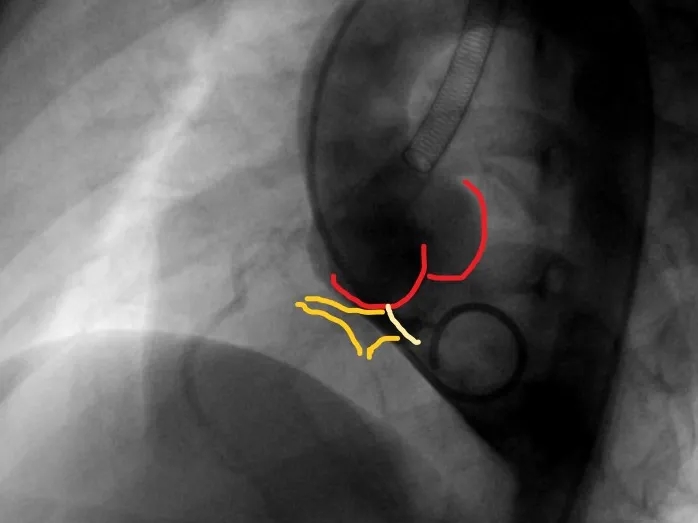

封堵器锁定后呈“蝴蝶状”明显盘状形态,室水平分流完全消失,主动脉瓣反流消失。

锁定后牵拉及释放

牵拉试验,封堵器稳定无移位,释放封堵器后超声下确认无残余分流,无主动脉瓣反流,三尖瓣反流同术前无增加。

大动脉短轴切面,封堵器释放后双盘紧贴间隔,呈现完美“工字形蝴蝶形”,顺应VSD形态及瓣膜形态。

MemoSorb全降解VSD封堵器展现了极佳的顺应性,在通过长隧道、小出口的VSD后,能顺利从“长哑铃”形态展开并固定为贴壁良好的“蝴蝶”形态。术后即刻超声评估显示,伞盘封堵完全,对相邻瓣膜无任何影响,主动脉瓣及三尖瓣均未出现反流。